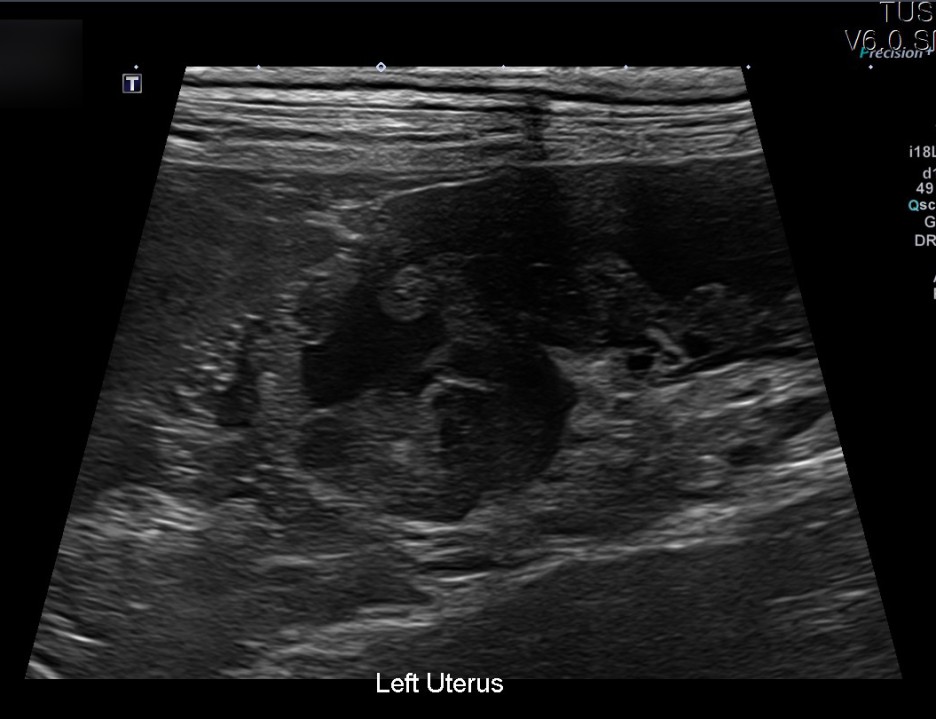

이어 진행된 초음파 검사에서는 자궁축농증으로 인해 내막이 두꺼워지고 크기가 커지는 염증성 변화가 진행되고 있었습니다.

✔US 양 자궁내막증식, 자궁각내삼출물에 의한 심한 확장소견